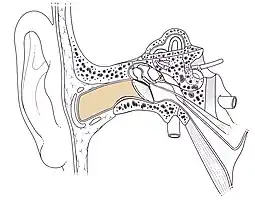

Conduit auditif externe droit (Ostéologie)